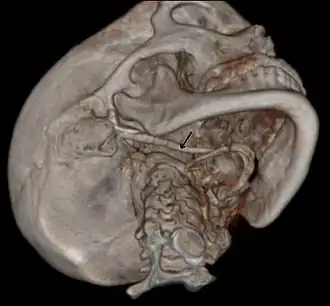

3D-reconstructed CT scan showing bilateral stylohyoid ligament ossification -

Diagnosis is suspected when a patient presents with the symptoms of the classic form of "Eagle syndrome" e.g. unilateral neck pain, sore throat or tinnitus. Sometimes the tip of the styloid process is palpable in the back of the throat. The diagnosis of the vascular type is more difficult and requires an expert opinion. One should have a high level of suspicion when neurological symptoms occur upon head rotation. Symptoms tend to be worsened on bimanual palpation of the styloid through the tonsillar bed. They may be relieved by infiltration of lidocaine into the tonsillar bed. Because of the proximity of several large vascular structures in this area this procedure should not be considered to be risk free.

Imaging is important and is diagnostic. Visualizing the styloid process on a CT scan with 3D reconstruction is the suggested imaging technique.[13] The enlarged styloid may be visible on an orthopantogram or a lateral soft tissue X ray of the neck.